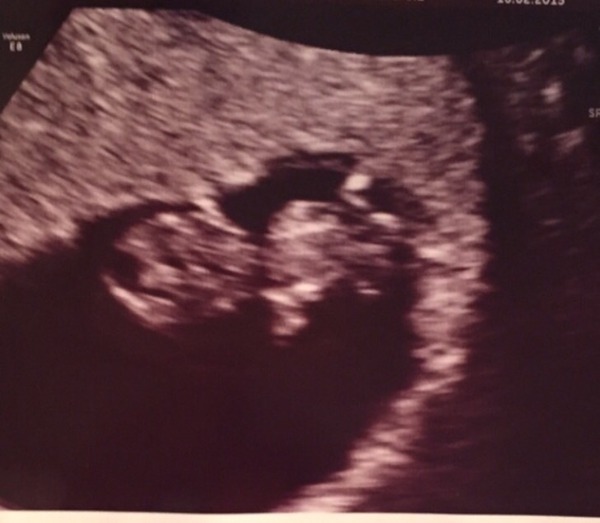

nutella fab scan photo!

What lovely pictures snow and nutella! How exciting. Well done on surviving the first trimester, Nutella!

nutella beaut little pic! Hurrah!!!

nutella I showed DH your scan pic and he said 'woah it's huge'. He must think it's a full grown baby already Grin idiot.